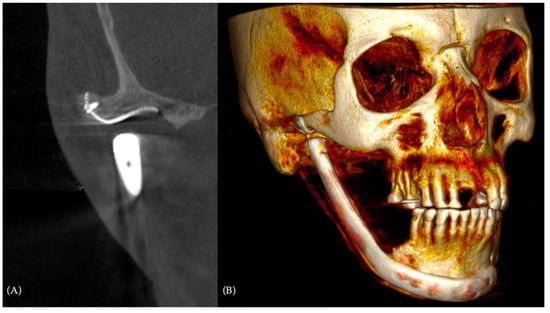

A postoperative CT scan was performed to check the prosthesis positioning and to have a comparison with the preoperative situation (Figure 6).

With almost 3 years of follow-up, a complete back to normal life was achieved, with a significant improvement in the overall quality of life. A CT scan at a 3-year follow-up showed perfect fitting of both alloplastic prosthesis elements to the bone (Figure 8).

Figure 8. The 3-year-follow-up CT scan: (A) detail of the appropriate fitting of the alloplastic fossa to the temporal bone in coronal view; (B) three-quarter right view of the CT scan 3D reconstruction, showing stability of the obtained result.